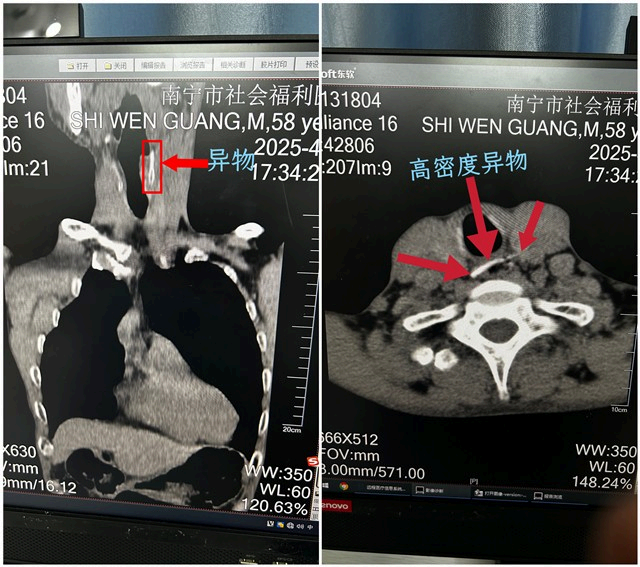

近日,我院放射科凭借精准的影像诊断,成功识别一例危急的食道异物病例,为临床团队实施救治提供了决定性依据,助力患者赢得宝贵救治时间,展现了医院在急危重症应对中的高效协作与专业水平。 日前,精神科患者小施(化名)于晚餐期间突发剧烈呛咳、呼吸窘迫。接诊医师高度怀疑食道异物梗阻,随即启动应急流程,将患者紧急送至放射科进行CT检查。放射科团队迅速响应,检查发现其胸椎第1-2椎体层面食管内存在一条状高密度异物影,呈左下至右上斜行,...